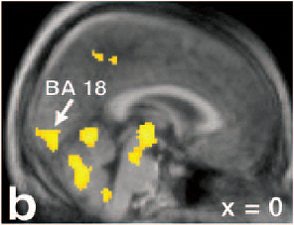

![]() |

| Sagittal view of the activations in midline cortical structures, the mesodiencephalic transition zone, and the cerebellum. Increased rCBF is represented in sagittal sections, of which the location is indicated by the red lines on the glass brain (above). |

The volunteers were asked to perform the following tasks twice: rest, erection, sexual stimulation/manual manipulation by a female partner, and ejaculation. The participants were asked to ejaculate within the first 50 seconds after the arrival of the tracer to the brain; eight subjects were successful.

The authors reported the strongest activation at the mesodiencephalic junction, including the ventral tegmental area (VTA), the subparafascicular nuclear, and the medial and ventral thalamus. Increased rCBF was also found in the anterior nucleus of the right thalamus and in the inferior temporal cortex.

![]() ![]() |

Activations are superimposed on the averaged MRI of the volunteers. Activation in the secondary visual cortex (b, BA 18) and the posterior cingulate/precuneus (c, BA 23/31) can be found. Note in sections a-c that the activation in the mesodiencephalic transition zone (mes-di) extends from the rostral midbrain into the ventral parts of the caudal thalamus x = 12 mm left to the intercommissural line. Holstege G, Georgiadis JR, Paans AM, Meiners LC, van der Graaf FH, Reinders AA, "Brain activation during human male ejaculation," J Neurosci 2003 Oct 8:23(27):9185-93. Copyright 2003 by the Society for Neuroscience.

Finally, "remarkably strong rCBF increases were observed in the cerebellum," they said. "These findings corroborate the recent notion that the cerebellum plays an important role in emotional processing."